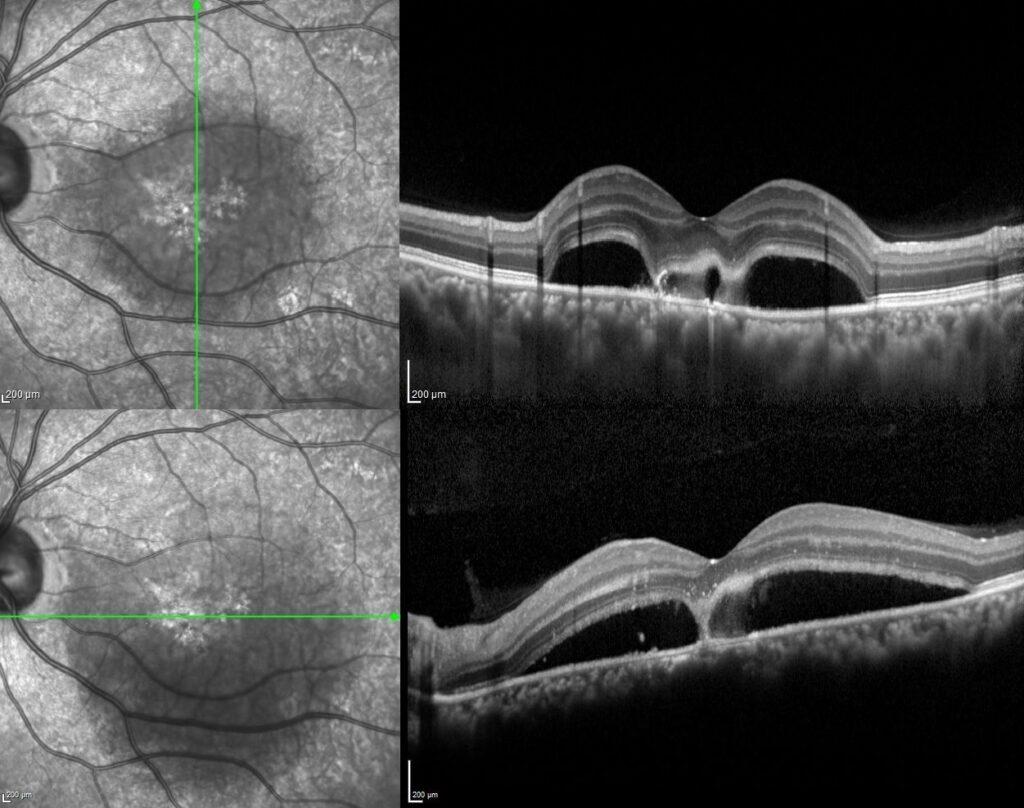

Dilated fundus examination demonstrated while the posterior segment of the right eye was completely normal, in the left eye there was a well-defined diffuse serous retinal detachment, a yellowish subretinal fibrinous material accumulation adjacent to the fovea, and a darker spot within the yellowish fibrin.

The spectral domain OCT scan passing through the area of fibrinous material revealed serous detachment, hyper-reflective fibrinous material accumulation extending from the RPE to the subretinal area within the detachment area, and two vacuolar structures visible as hyporeflective spaces amid the hyper-reflective fibrin.

Optic coherence tomography has an important role in the diagnosis and follow-up of central serous chorioretinopathy. Several OCT studies have demonstrated hyper-reflectivity in the subretinal space corresponding to the fibrin material and have also demonstrated dipping of the neurosensory retina at the site of fibrin formation. Sometimes, this fibrin accumulation has hyporeflective areas and has been named the vacuole sign. It was reported that the presence of a hyporeflective vacuole amid the hyper-reflective fibrin adjacent to RPE defects probably indicates the site of constant fluid egress. It was also emphasized that the vacuol sign could be an important indicator of disease activity, especially in cases where angiography is not possible.